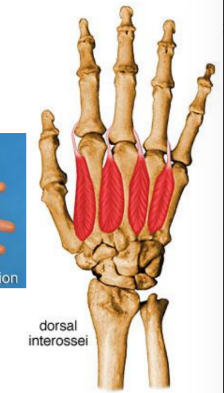

Interossei, palmar and lumbricals

ORIGIN | INSERTION | ACTION | INNERVATION | |

Dorsal interossei (4) | Adjacent sides of two metacarpals | Extensor expansions and base of proximal phalanges of digit 2-4 | Abduct digits from axial line Act with lumbricals to flex metacarpophalangeal joint and extend interphalangeal joint | Deep branch of ulnar nerve |